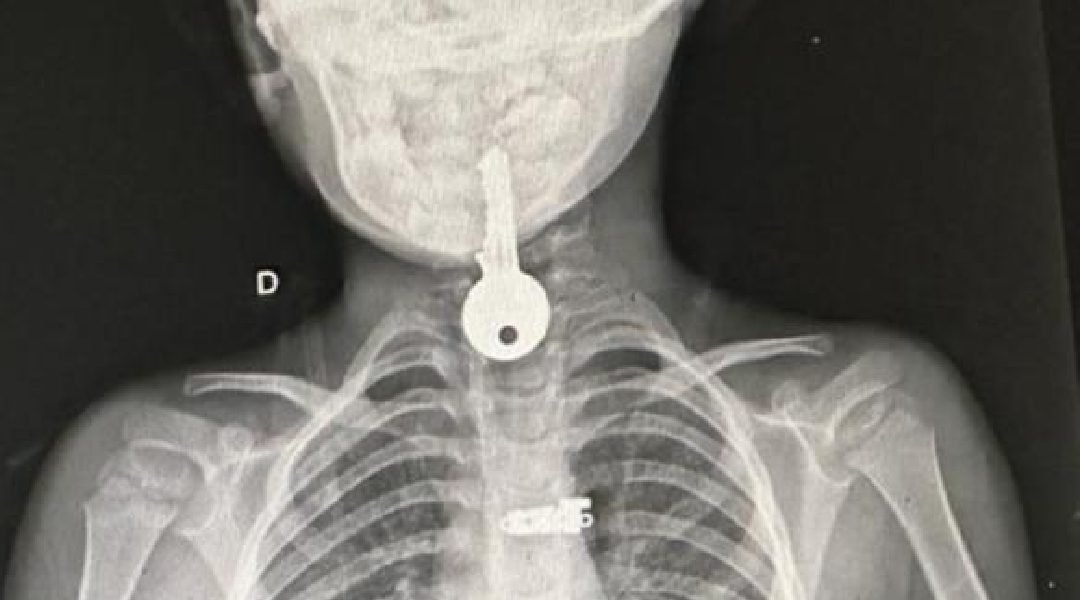

Um menino de apenas quatro anos de idade, residente no município de Porto Walter, passou por um susto na última segunda-feira, dia 6, ao engolir uma chave. O menino foi encaminhado via Tratamento Fora de Domicílio (TFD) ao Hospital Regional do Juruá em Cruzeiro do Sul, já que o hospital do município não oferece suporte para este tipo de emergência. Atualmente o hospital funciona em um edifício que era utilizado como Unidade Básica de Saúde (UBS), pois, o prédio onde funcionava a unidade hospitalar, está em obras de reforma desde 2022, com a promessa de que a construção duraria apenas três meses.

Após os devidos procedimentos médicos, os especialistas conseguiram retirar a chave, que estava presa no esôfago da criança. Felizmente, o pequeno paciente encontra-se em bom estado de saúde e em breve poderá retornar para casa.